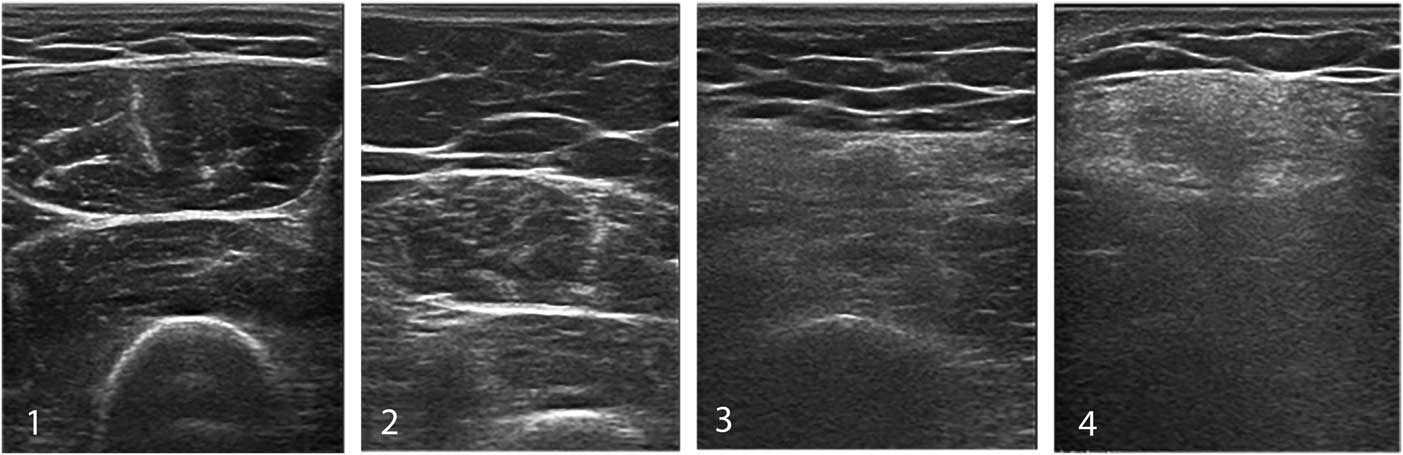

To improve diagnostic sensitivity, a semi-quantitative score such as the Heckmatt grading scaleReference Heckmatt, Leeman and Dubowitz 24 (Figure 13) can be used to rate the echogenicity of muscle images. Heckmatt grade I corresponds to the appearance of normal muscle, with clearly visible muscle architecture and minimal attenuation of the ultrasound beam, so that underlying structures such as bone and fascial planes are clearly visible. Heckmatt grade 2 denotes a slight overall increase in echogenicity (i.e., whiteness) of the muscle, without attenuation of the underlying structures. Grade 3 shows a further increase in whiteness and some attenuation with reduced visibility of underlying structures; grade 4 shows a completely white muscle and strong attenuation with loss of visualization of the underlying bone or fascia echo.

Figure 13 The Heckmatt grading scale for visual assessment of muscle echogenicity. Grade 1 is normal. Grade 2 shows an overall increase in echogenicity without architecture loss or attenuation. Grade 3 showed clearly increased muscle echogenicity, loss of muscle architecture and some attenuation causing less visibility of deeper structures. Grade 4 denotes a completely white muscle with loss of recognizable features and strong attenuation of the ultrasound signal, so no deep structures can be discerned beyond the superficial layer of muscle.